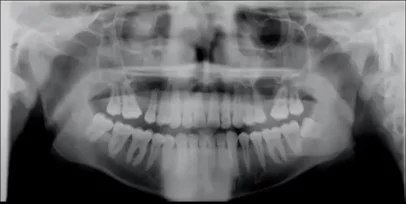

Dark area occluding maxillary apices

This is probably one of the most common problems we see with busy offices taking panoramic images. However, this symptom can be tricky to get rid of.

The most common root cause of this artifact is the patient failing to hold their tongue flat against the top of the hard palate. While most operators are aware of this recommended step, there are two additional lesser-known facts that may thwart dental professionals trying to remove this artifact from their images.

First, simply telling the patient to “put your tongue to the top of your mouth” may not solve this problem. The reason for this is that many patients may take this direction to mean they should simply touch the roof of their mouth with the tip of their tongue. This approach will not solve this problem because the goal is to remove the air gap between the tongue and the hard palate. Instead, we recommend that the operator should instruct the patient to “press the tongue flat against the roof”, which will better remove the air gap that can cause this artifact.

Another challenge for the office is that there is a very similar-looking artifact that may present for a completely different reason. If a large cross sectional area of the hard palate is between the x-ray source and the mandibular apices, this can absorb x-rays exposing this region, and can result in the dark artifact. This can be caused if the occlusion of the patient is “too flat”. The ideal approach to avoid this is to position the patient with a slight (~10 degree) downward tilt of the occlusal plane.